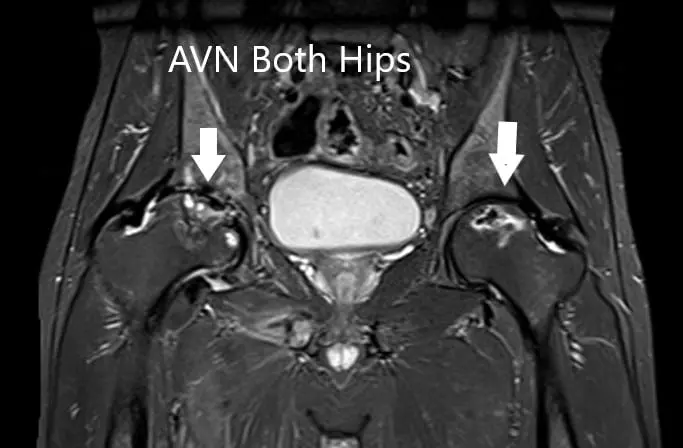

MRI suggested marked signal attenuation of bilateral femoral heads. There was a collapse of the right head and precollapse stage 2a of the left hip.

MRI showing bilateral femoral head AVN in T2WI